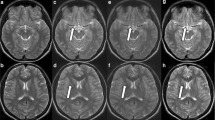

Three-dimensional turbo spin echo T1-weighted imaging was performed in 14 healthy volunteers (mean age, 57 years; range, 33–67 years; 7 men) under SENSE and CS with accelerator factors of 5.5, 6.8, and 9.7. Eight anatomical locations (brain parenchyma, salivary glands, masseter muscle, tongue, pharyngeal mucosal space, eyeballs) were evaluated. Reproducibility of radiomic features was evaluated by calculating concordance correlation coefficient (CCC) in reference to the original image (SENSE with acceleration factor of 3.5). Reproducibility of radiomic features among acceleration factors and between SENSE and CS was compared.

Proportion of radiomic features with CCC > 0.85 in reference to the original image was lower with higher acceleration factors in both SENSE and CS across all anatomical locations (p < .001). Proportion of radiomic features with CCC > 0.85 in reference to the original image was higher in SENSE compared with CS (SENSE, 6.7–7.3% vs CS, 4.4–5.0%; p < .001). Run percentage of gray-level run-length matrix (GLRLM) with wavelet D showed CCC > 0.85 in reference to the original image in both SENSE and CS at acceleration factor of 9.7 in the highest number of anatomical locations.

Higher acceleration factors resulted in lower reproducibility of radiomic features in both SENSE and CS, and SENSE showed higher reproducibility of radiomic features than CS in reference to the original image. Run percentage of GLRLM with wavelet D was identified as the most reproducible feature.